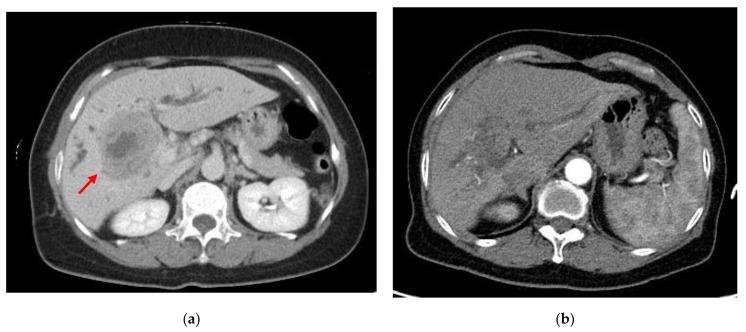

Primary squamous cell carcinoma (SCC) of the liver is a rare disease that is difficult to diagnose until the pathology is confirmed. The age of the patients generally ranges from 18 to 83 years. The pathogenesis of primary SCC of the liver remains unclear and therapeutic guidelines have not yet been established. The overall survival rate may be less than 1 year. The prognosis for patients without surgery is worse than that for patients who undergo surgery. Herein, we report a case of primary SCC of the liver that responded well to intravenous carboplatin and 5-flurouracil (5-FU) with the aim of providing an alternative therapeutic option. A 61-year-old woman with no history of alcohol use disorder, cirrhosis, exposure to hepatotoxic chemicals, or a remarkable family history presented to our hospital with a complaint of epigastric pain, poor appetite, and fatigue, which had occurred 3 days before presentation. Blood tests revealed levels of alpha-fetoprotein of <2.0 ng/mL, carcinoembryonic antigen of 4.39 ng/mL, carbohydrate antigen (CA) 19-9 of 1306.15 U/mL, CA 125 of 66.3 U/mL, CA 153 of 19.7 U/mL, and SCC antigen of 8.5 ng/mL. Computed tomography scans of the abdomen showed a 5.8-cm lobulated soft-tissue mass with central necrosis in segment 6 of the liver, which caused compression of the common hepatic duct. Pathological examination of the masses revealed squamous cell carcinoma with focal glandular differentiation. The patient underwent palliative chemotherapy with intravenous carboplatin 150 mg (day 1) and 5-FU 1000 mg (days 1−4) instead of surgery. After two cycles of chemotherapy, jaundice and liver function improved. The patient was discharged in stable condition and was followed up in our outpatient department. Although the patient refused to undergo surgery, no tumor recurrence or distant metastasis was found during the 8-month follow-up period. This report highlights that neoadjuvant chemotherapy with carboplatin and 5-FU can be considered for primary SCC of the liver before a liver resection.

原发性肝细胞鳞状细胞癌(SCC)是一种罕见疾病,在病理确诊前难以诊断。患者的年龄一般在 18 岁至 83 岁之间。原发性肝细胞 SCC 的发病机制尚不清楚,也尚未制定治疗指南。总体存活率可能不到 1 年。未手术的患者预后比手术的患者差。在此,我们报告了一例对静脉注射卡铂和 5-氟尿嘧啶(5-FU)反应良好的原发性肝细胞 SCC 病例,旨在提供一种替代的治疗选择。一位 61 岁的女性,无酒精使用障碍、肝硬化、接触肝毒性化学物质或显著家族史,因上腹痛、食欲不振和疲劳就诊,这些症状在就诊前 3 天出现。血液检查显示甲胎蛋白水平<2.0ng/mL,癌胚抗原 4.39ng/mL,糖类抗原(CA)19-9 为 1306.15U/mL,CA 125 为 66.3U/mL,CA 153 为 19.7U/mL,鳞状细胞癌抗原为 8.5ng/mL。腹部计算机断层扫描显示肝脏 6 段有一个 5.8 厘米分叶状软组织肿块,中央有坏死,压迫肝总管。肿块的病理检查显示为鳞状细胞癌,伴有局灶性腺分化。患者接受了静脉注射卡铂 150mg(第 1 天)和 5-FU 1000mg(第 1-4 天)的姑息性化疗,而非手术。两个周期的化疗后,黄疸和肝功能改善。患者病情稳定出院,并在我院门诊进行随访。尽管患者拒绝手术,但在 8 个月的随访期间未发现肿瘤复发或远处转移。本报告强调,在进行肝切除术前,卡铂和 5-FU 的新辅助化疗可考虑用于原发性肝细胞 SCC。